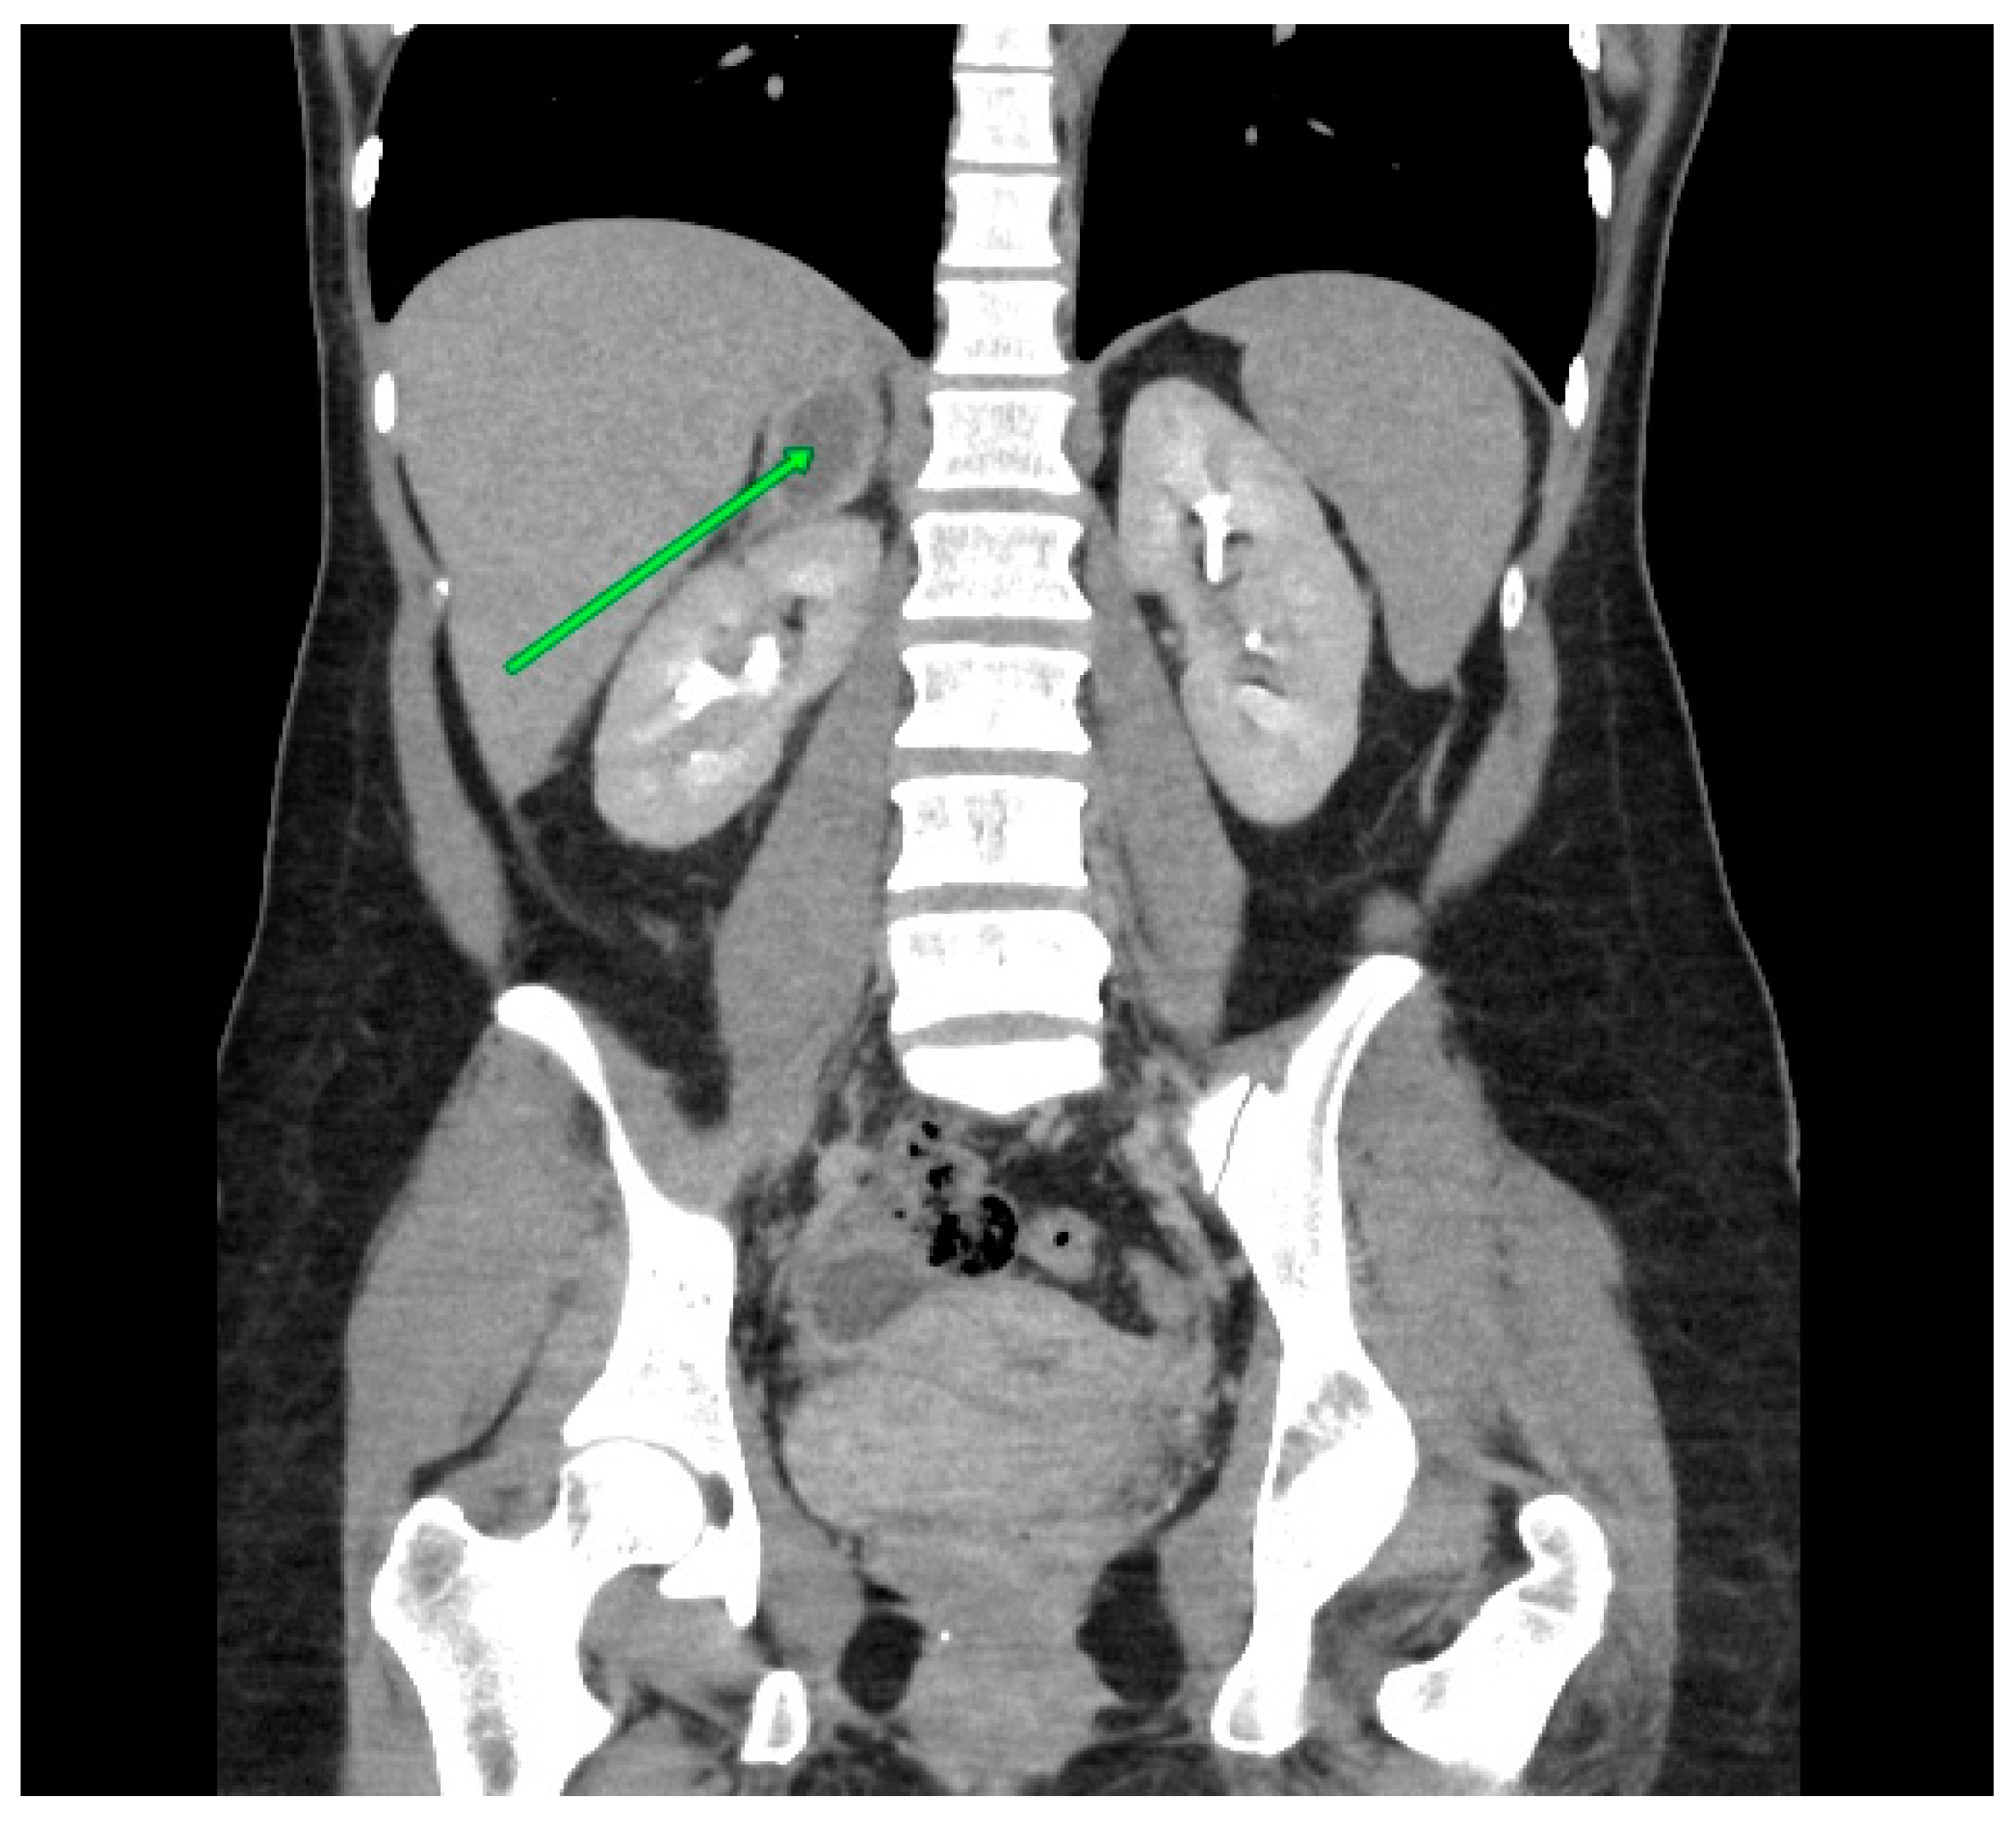

Imaging was conducted in the clinic, commencing with an ultrasound. The imaging results demonstrated the presence of a heterogeneous lesion in the projection of the right adrenal gland. The lesion exhibited a mixed echogenicity and measured 123 × 59 × 53 mm. A Doppler scan revealed no vascularity. Four days later, an MRI scan was conducted. The scan revealed the presence of a hematoma in the right adrenal gland with dimensions of 12 × 7.3 × 6.7 cm. The lesion exhibited a heterogenous, mixed-signal in both T1- and T2-weighted images. The lesion compressed and displaced the right kidney. A solid mass measuring 2.1 cm in width was identified in the vicinity of the right kidney, and it was suspected to be a hematoma. Furthermore, a thin smudge of blood was identified along the lower edge of the liver. Additionally, a minor hydronephrosis was observed in the vicinity of both kidneys (Figure 1).

Figure 1. An abdominal MRI, revealed a hematoma in the right adrenal gland.